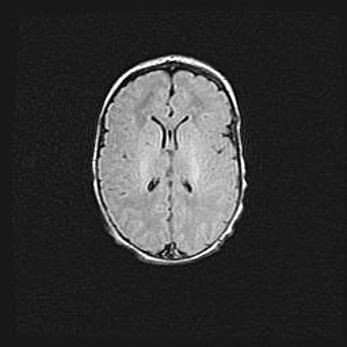

Наружная гидроцефалия с возможной атрофией височных областей.

Возраст: 28 дней

Вес: 3670 г

Пол: мужской

Окружность головы: 38 см

Срок гестации: 40 недель

Гидроцефалия головного мозга у новорожденных – это заболевание, которое характеризуется скоплением избыточного количества спинномозговой жидкости в желудочковой системе головного мозга в результате затруднения её перемещения от места выработки к месту поглощения в кровеносную систему или вследствие нарушения абсорбции. При открытой наружной форме гидроцефалии у новорожденных расширяются и переполняются субарахноидные пространства.

При нормотензивных  формах,  которые,  как  правило,  являются  следствием  перенесенных ишемических  повреждений  паренхимы  мозга,  возможно  сочетание микроцефалии  с нормотензивной гидроцефалией. В основе данных изменений лежит атрофия больших полушарий с преимущественной  локализацией  в  лобно-височных  областях.